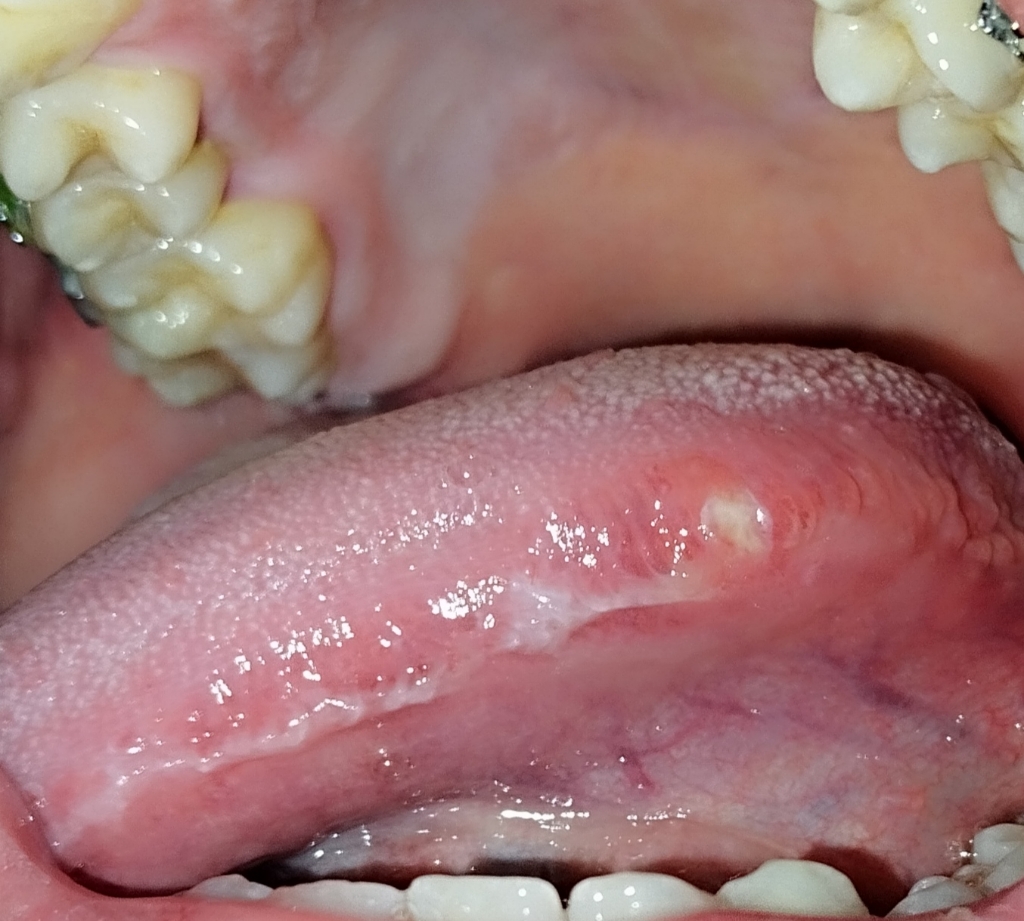

Em chào bác sĩ em là nam 20 tuổi hôm qua em có cảm giác hơi khó chịu ở vùng cạnh lưỡi và đi soi gương phát hiện ra có 1 vết trợt nhỏ màu trắng đến hôm nay bắt đầu đau nhiều và đau lan lên tai, nó gây đau và rất khó khăn khi ăn và nói chuyện, vết trợt này không chảy máu, không có mùi, sờ vào mềm không chai cứng bác sĩ cho em hỏi đấy có phải vết nhiệt ở lưỡi không hay là ung thư lưỡi ạ, và bác sĩ có thể nói cụ thể hơn về ung thư lưỡi không ạ ? Em có cần thiết phải đi sinh thiết không ? Hiện tại em đang rất lo lắng mong bác sĩ trả lời giúp em. Em cảm ơn bác sĩ nhiều

Em chụp rõ hơn rồi ạ vậy nó cũng chỉ là vết loét nhiệt miệng thông thường thôi đúng k ạ ?

Vết loét thông thường không có yếu tố ung thư